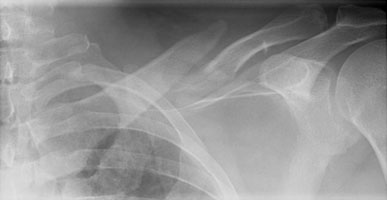

- Click on the image for a larger versionAAP radiograph of the left clavicle. There is an acute mid-clavicular fracture.